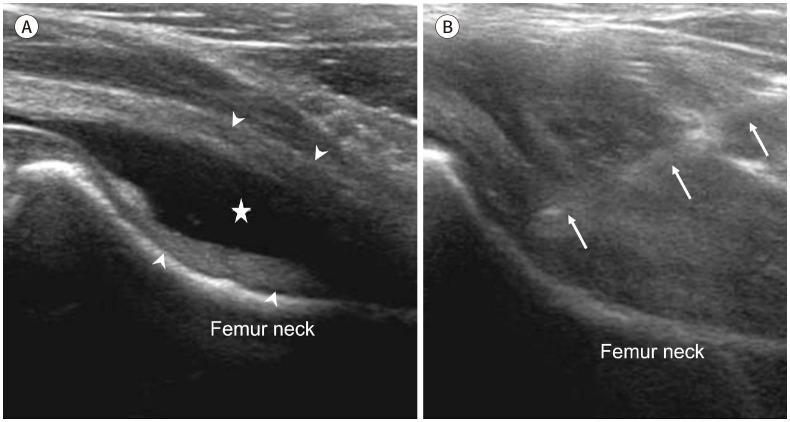

Developmental dysplasia of the hip is a condition characterized by hip joint instability due to acetabular dysplasia in infancy, necessitating precise ultrasound examination. Legg-Calvé-Perthes disease is caused by a temporary disruption in blood flow to the femoral head during childhood, progressing through avascular, fragmentation, re-ossification, and residual stages. Slipped capital femoral epiphysis is a condition where the femoral head shifts medially along the epiphyseal line during adolescence due to stress, such as weight-bearing. Differentiating between transient hip synovitis and septic arthritis may require joint fluid aspiration. Osteomyelitis can be associated with soft tissue edema and osteolysis. When multiple lesions are present, it is essential to distinguish between Langerhans cell histiocytosis and metastatic neuroblastoma. This review will introduce imaging techniques and typical findings for these conditions.

发育性髋关节发育不良是一种因婴儿期髋臼发育不良导致髋关节不稳定的病症,需要进行精确的超声检查。Legg-Calvé-Perthes病是由儿童期股骨头血液供应暂时中断引起的,历经缺血、碎裂、再骨化和残留阶段。股骨头骨骺滑脱是一种在青春期由于负重等压力导致股骨头沿骨骺线向内侧移位的病症。区分暂时性髋关节滑膜炎和化脓性关节炎可能需要进行关节液抽吸。骨髓炎可伴有软组织水肿和骨质溶解。当出现多个病灶时,区分朗格汉斯细胞组织细胞增多症和转移性神经母细胞瘤至关重要。本综述将介绍这些病症的影像学技术和典型表现。